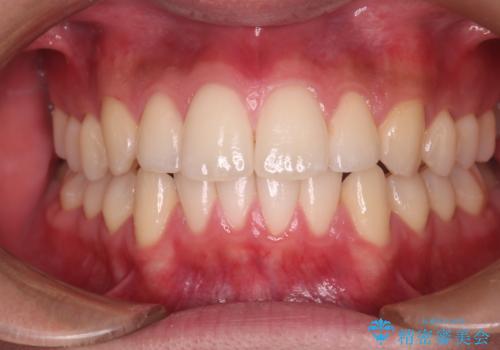

【クリア装置】八重歯とがたつきを綺麗に